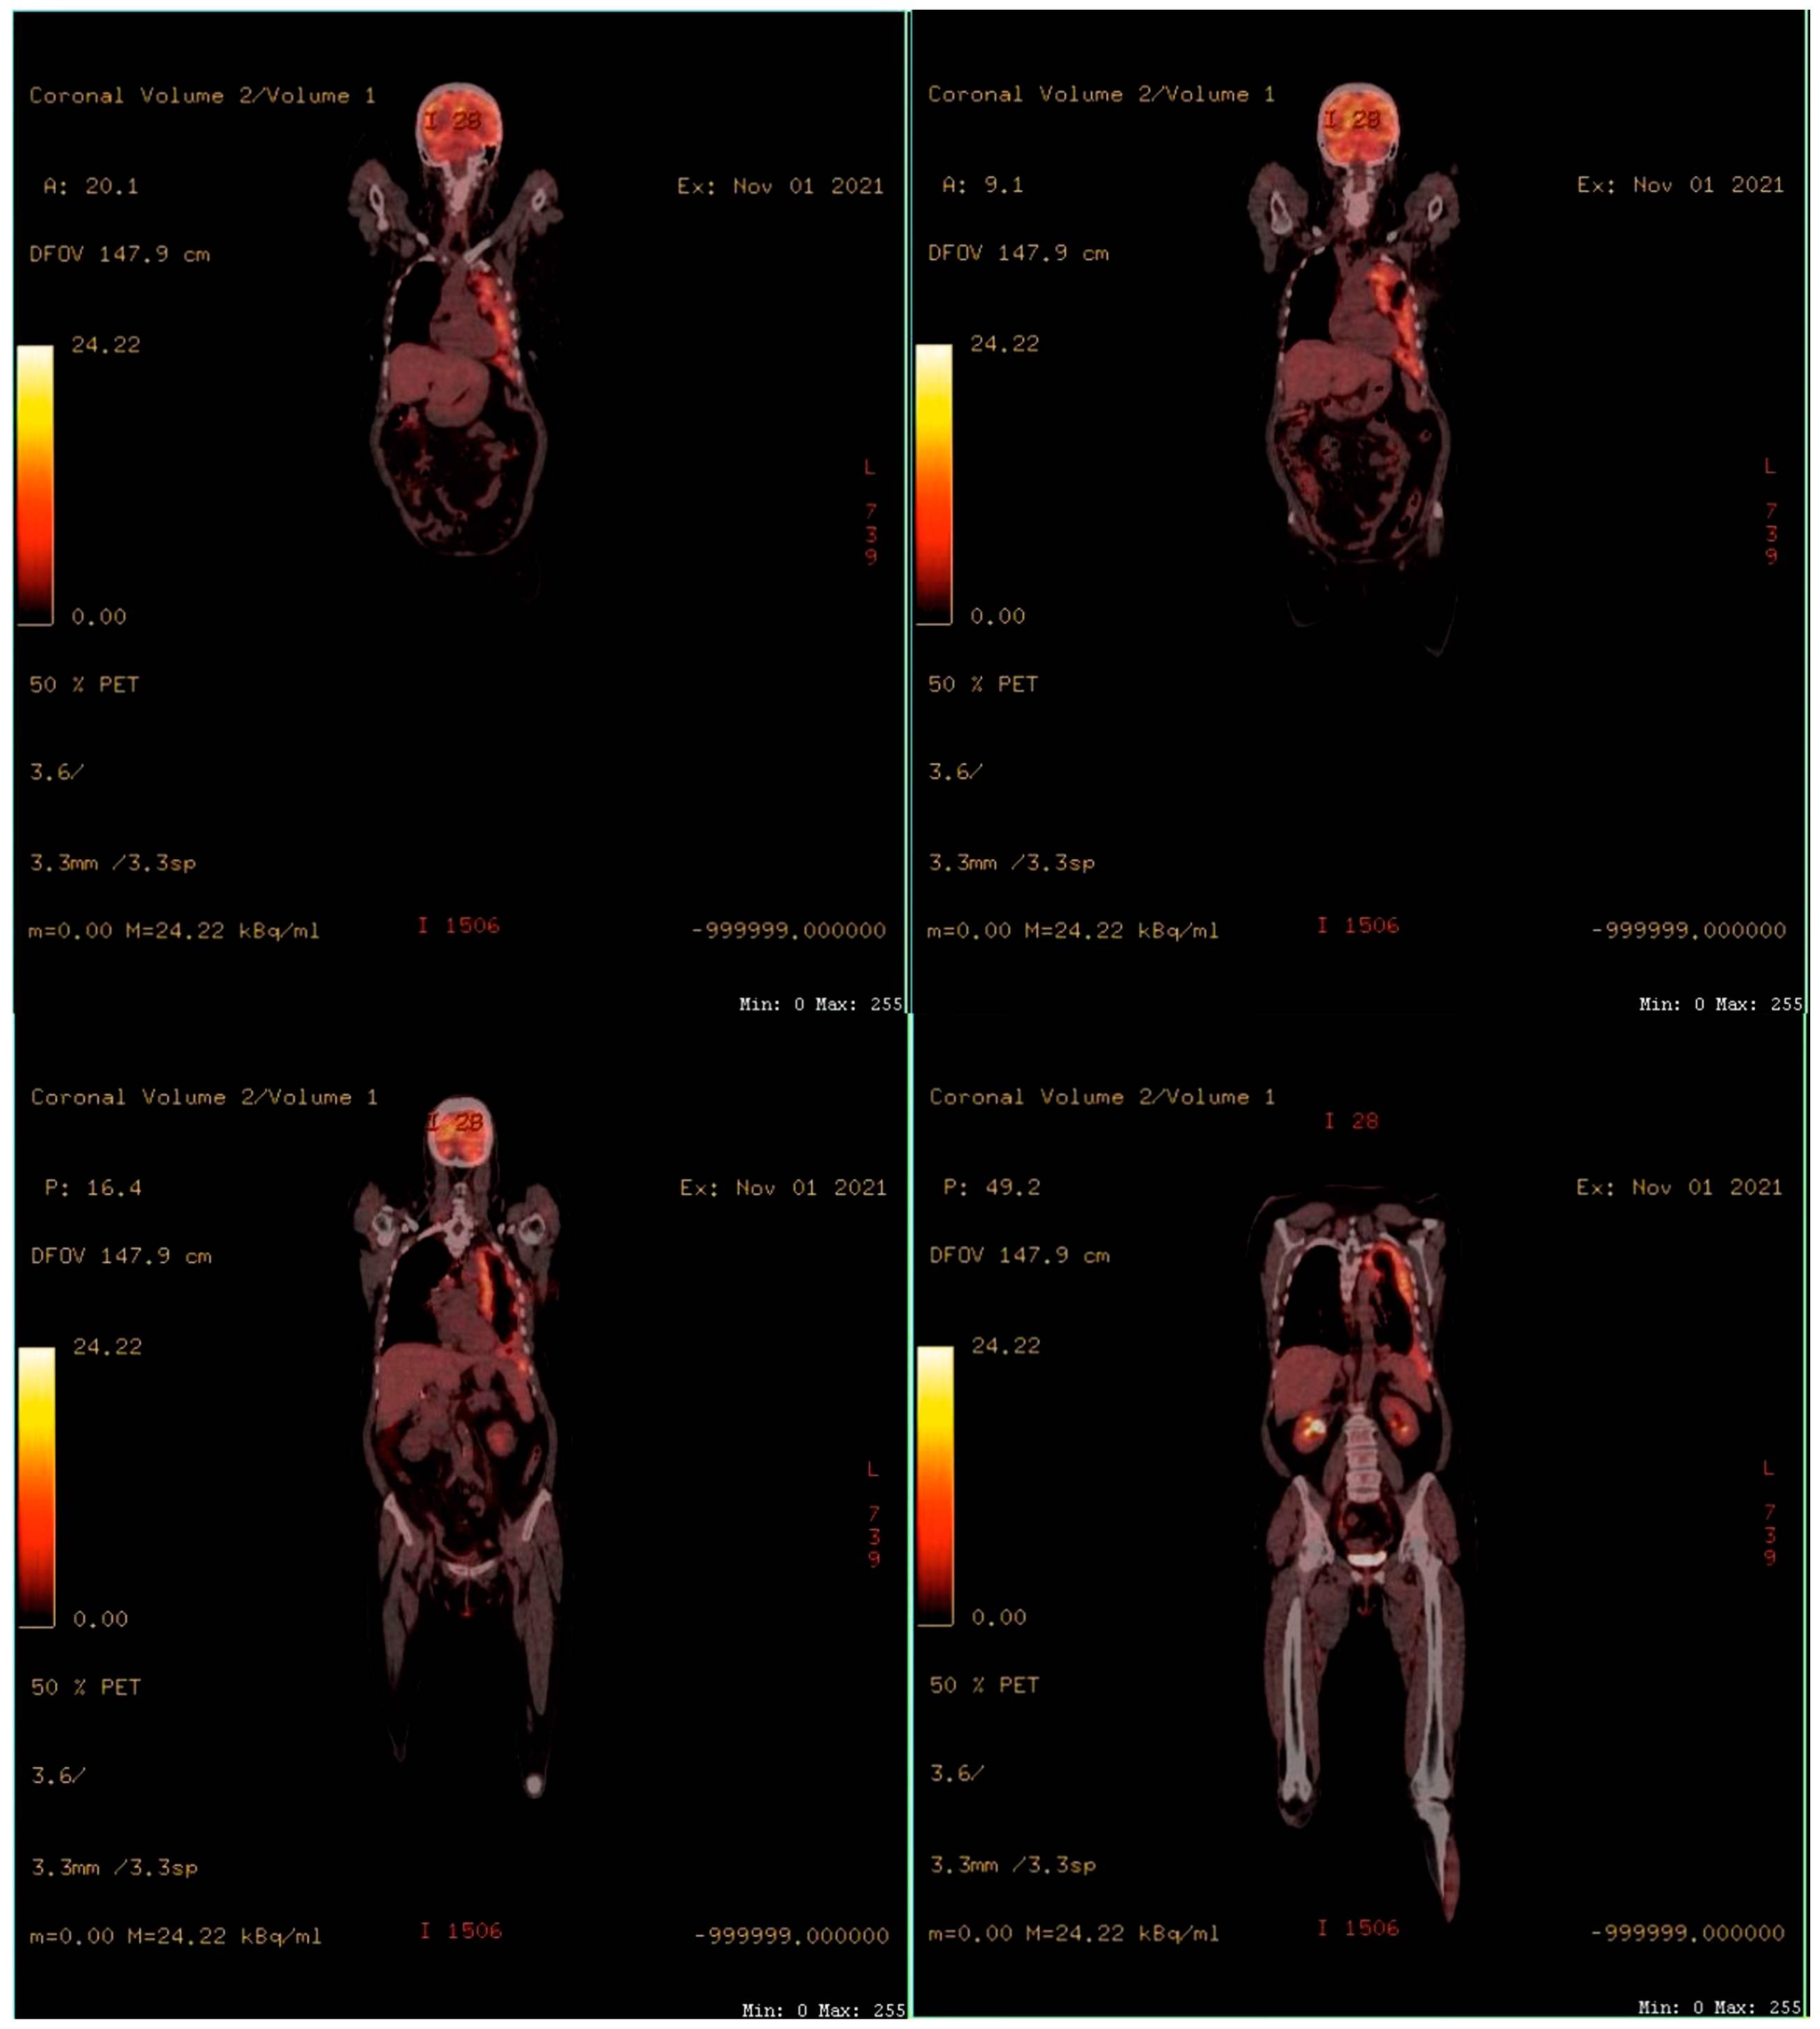

To assess the extension of the lesions, a positron emission tomography (PET-CT) was performed. The results showed the thickening of the left pleura from the top to the base. No metastases or invasion of the chest wall, mediastinum, or diaphragm were noted (Figure 2).

Figure 2.

PET-CT scans showing thickening of the left pleura from top to base. No metastases or invasion of the chest wall, mediastinum, or diaphragm.